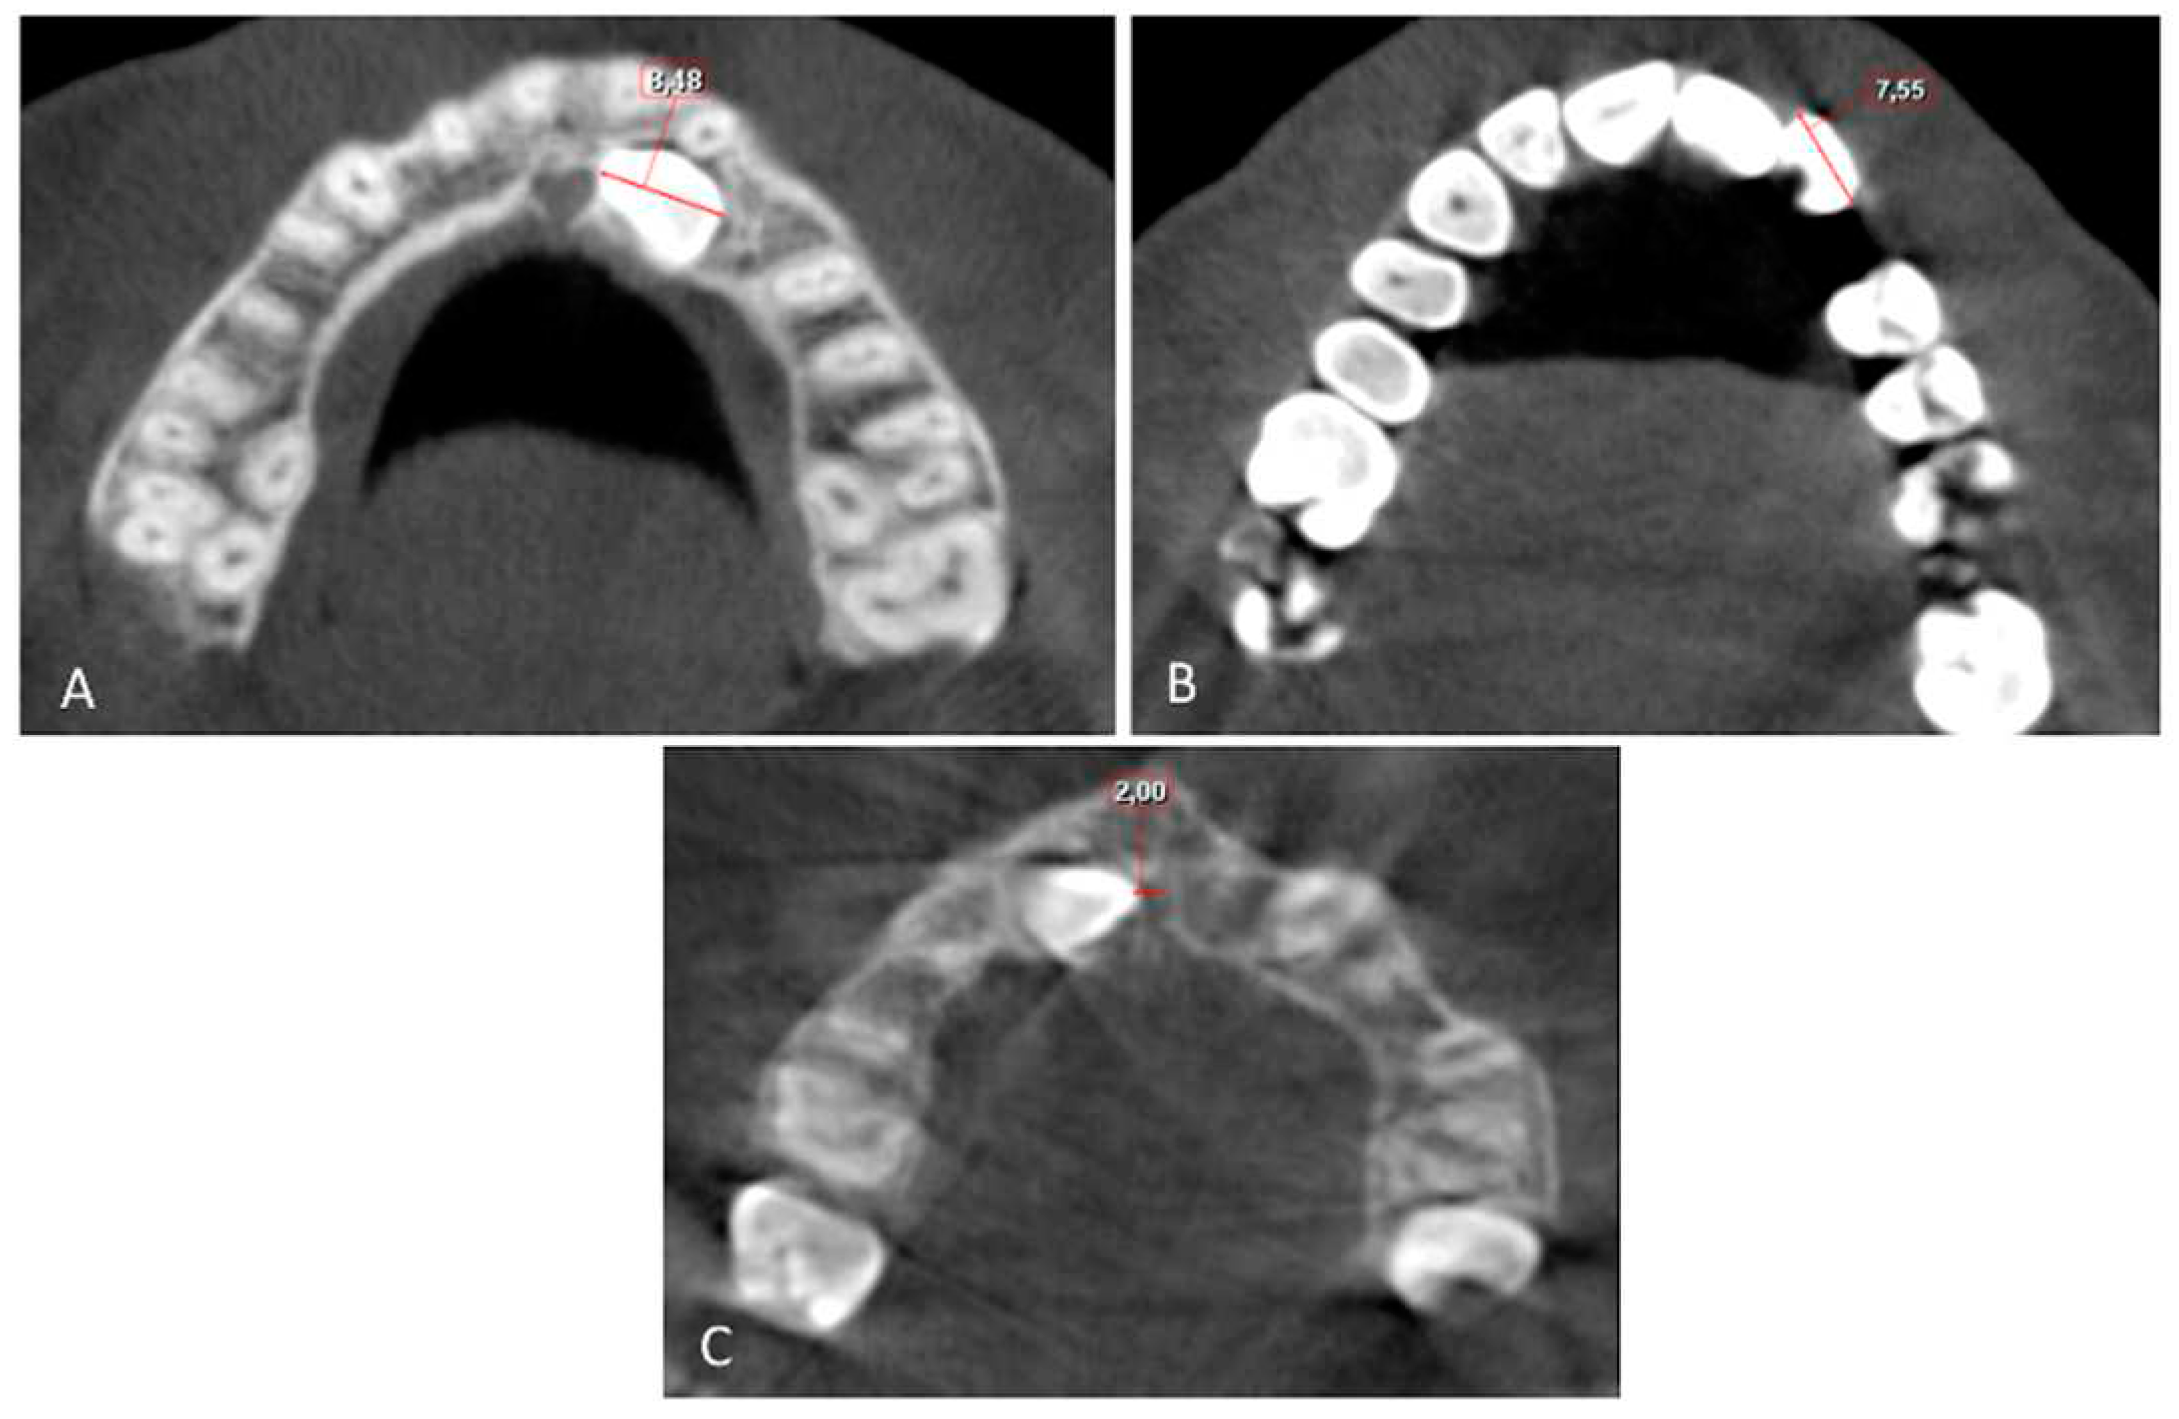

The buccolingual (BL) and mesiodistal (MD) widths of the crowns of the lateral incisor (U2) and canine (U3) were measured from the widest point of the crown perpendicular to the long axis on the sagittal and coronal sections, respectively (Figure 4 and Figure 5).

Root length (RL) was measured from the lowest level of the buccal cementoenamel junction (CEJ) to the root apex, and the total length (L) of the lateral incisor was measured from the incisal tip to the root apex on the sagittal section (Figure 5). The horizontal distance of the maxillary impacted canine (U3 HD) from the tip of the canine cusp to the midline was measured in the axial section. The vertical distance of the maxillary impacted canine (U3 VD) from the tip of the canine cusp to the occlusion plane was measured in the sagittal plane (Figure 4, Figure 5 and Figure 6).

Figure 4. A. Mesiodistal width of the canin crown (U3 MD) and B. Mesiodistal width of the lateral crown (U2 MD); the distance between widest points of the crown on the axial section. C. Horizontal Distance to midline from canine crown (U3 HD); distance from cusp tip of canine crown to the midline on the axial section.